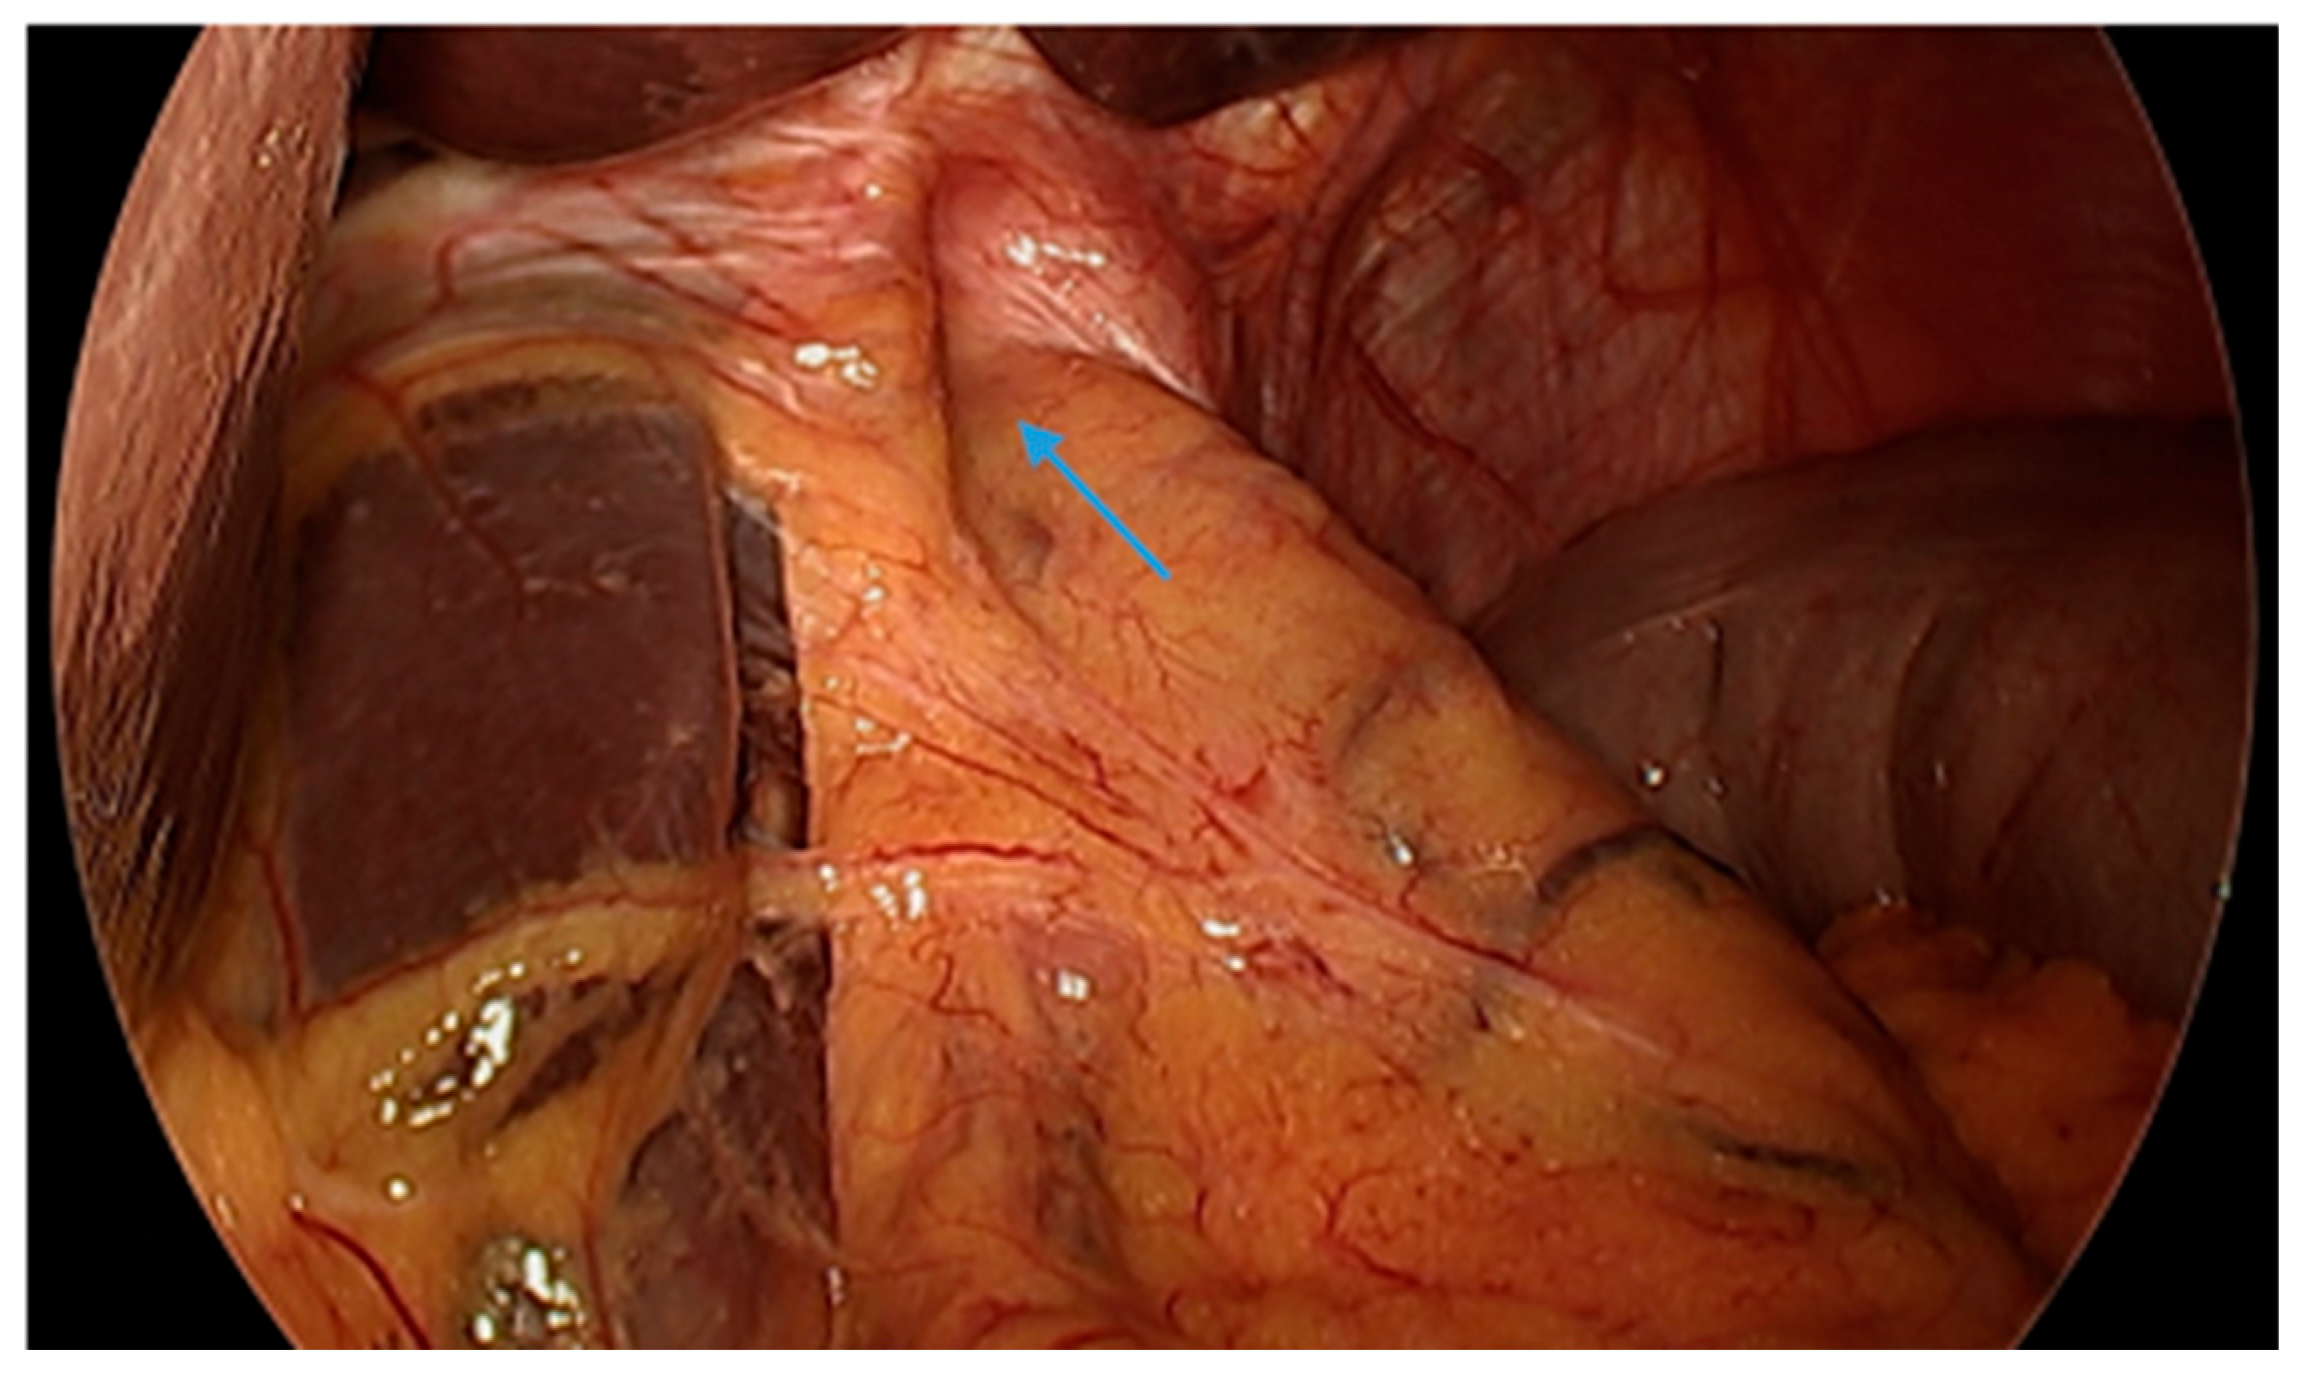

Figure 1.

Upper gastrointestinal series in a patient post-sleeve gastrectomy with early satiety and reflux reveals the following: a small, hiatal hernia and gastroesophageal reflux (blue arrow, left) in addition to abnormal angulation (blue arrow, right) and dilation of the gastric sleeve (green arrow, right). The patient underwent conversion to Roux-en-Y gastric bypass with marked clinical improvement.

Figure 2.

An upper gastrointestinal series reveals a moderate, sliding type-one hiatal hernia (bottom arrow) in addition to gastroesophageal reflux disease (top arrow) in a patient with morbid obesity.

Complications of SG, including stenosis, angulation or kinking, are associated with increased intragastric pressure and GERD (Figure 1) [38]. Data regarding the optimal bougie size for weight loss and reduced reflux are mixed, but generally support a range of 36–42 French [39,40,41,42,43]. Overfilling of the gastric sleeve due to a large meal portion may result in reflux symptoms, and thus, patients should be counseled to gradually advance their diet from liquids to small portions of healthy, protein-rich foods. The gastric sleeve dimensions should be sufficient, as too narrow of a gastric sleeve may result in increased intragastric pressure and subsequent reflux. An abnormally narrow sleeve may also lead to regurgitation due to overfilling, even in patients with a competent lower esophageal sphincter and no hiatal hernia. Felinska et al. described the ideal shape of a gastric sleeve to be a trapezoid with a wide antrum and a narrow cardia to prevent sleeve stenosis or increased pressure within the stomach [34]. Furthermore, the preservation of the antrum has been suggested to increase gastric emptying and reduce subsequent GERD [44]. Esophagogastric dysmotility may be a contributing factor to post-SG GERD and a dynamic contrast study can be a useful test in establishing the diagnosis.